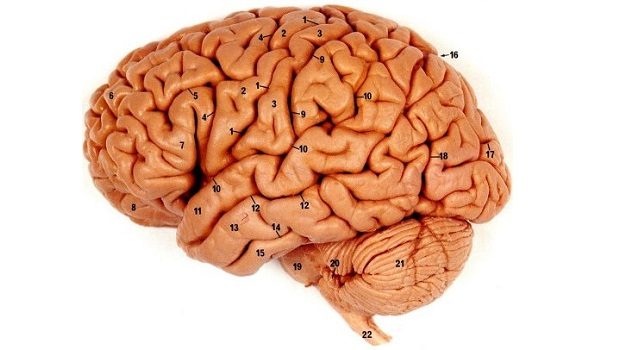

İlk olarak, eğer iddia edildiği gibi beynimizin %10’u çalışıyor, %90’ı çalışmıyor olsaydı, beyinde meydana gelen hasarların çok büyük bir kısmı etkisiz olacaktı. Çünkü 10’da 9’luk bir olasılıkla hasar beynin güya “çalışmayan” bir bölgesine denk gelecek ve etkisiz kalacaktı. Ancak şimdiye kadar yapılan araştırmalar göstermiştir ki, beynin herhangi bir bölgesinin aldığı hasar, vücudun herhangi bir noktasındaki herhangi bir işleyişi neredeyse her zaman, istisnasız bozmaktadır. Beynin aldığı en ufak hasarlar bile, çok ciddi problemlere ve hastalıklara sebep olabilmektedir. Örneğin beyin tomografinizde, beynin bir bölgesinde bulunan bir kıvrımın açısının 1-2 derece farklı olarak çıkması, sizin psikolojik durumunuzun değişiminin sebebi ve hatta ölümcül bir hastalık belirtisi olabilmektedir. Yani beynin herhangi bir kısmının işlevsiz olduğu iddiası geçersizdir.

Üçüncü açıklama ise gelişen görüntüleme tekniklerinden gelmektedir. Pozitron Emisyonlu Tomografi (PET) ve Fonksiyonel Manyetik Rezonans İmgeleme (fMRI) teknolojilerindeki gelişmeler sayesinde, beynin renkli ve renksiz, ayrıntılı fotoğrafları an be an çekilebilmektedir. Bu teknolojiler sayesinde günümüzde biliyoruz ki, beynin en sakin olmasını umduğumuz uyku halinde bile, beynin eksiksiz olarak her bölgesinde belli bir miktar aktivite gerçekleşmektedir.

Dördüncü bir açıklama, yine tıp alanından gelmektedir. Günümüzde, nöroloji bilimi sayesinde artık biliyoruz ki, beynin tamamen “sustuğu” tek durum, ciddi sinirsel hastalıklar ve beyin hasarları durumunda gerçekleşmektedir. Yani beyin, yukarıda açıkladığımız gibi uyku halinde bile tamamen durmamakta, tam tersine beynin her alanından az ya da çok sinyal alınabilmektedir.

Beşinci bir açıklama anatomiden gelmektedir: beyin tek bir bütün olarak çalışmaz; onlarca, hatta yüzlerce alt birimi vardır. Daha bilimsel bir açıklamayla, beyin “ileri derecede özelleşmiş bir organ”dır. Bu sebeple, parçaların çalışmaması gibi bir durum söz konusu olamaz; çünkü bu beynin kendisinin çalışmaması demektir. Beynin parçalara ayrılması sayesinde beynin her bölgesinin tam olarak çalıştığı kesinlikle bilinmektedir. 1800’lü yılların sonlarında atılan iddia, beynin bir bütün olarak çalıştığını düşünmekten kaynaklanmaktadır. Günümüz insanları ise 200 yıl öncesinin bilgisini ısrarla yaymaya devam etmektedirler.

Altıncı bir açıklama, hücrelerin dünyasına daha derin bir şekilde dalabilmemizden gelmektedir. Beyinde bulunan sinir hücreleri ve doku hücreleri üzerinde yapılan mikroskobik çalışmalar, beynin her bir hücresini inceleyebilmemizi sağlamaktadır. Tekil-Birim Kaydı (Single-Unit Recording) ismi verilen bu teknoloji sayesinde beyne yerleştirilen elektrotlarla, beyindeki her bir hücrenin anlık aktivitesi gözlenebilmektedir. Onlarca yıldır süren ve beynin her alanına yayılmış araştırmalarda, çalışmayan tek bir hücreye bile rastlanmamıştır.

Yedinci bir açıklama, metabolik çalışmalardan gelmektedir. Bu alandaki yapılan araştırmalarda beyne radyoaktif olarak işaretlenmiş 2-deoksiglukoz molekülleri enjekte edilir. Daha sonra radyograf aracılığıyla hangi hücrelerin aktif olduğu parlak bir şekilde gözlenebilir. Eğer iddia edildiği gibi beynin %90’ı çalışmıyor olsaydı, radyografta beynin %90’ı karanlık olarak çıkması gerekirdi. Ancak yapılan araştırmalar, beynin her bir noktasının çalıştığını göstermektedir.

Son bir açıklama da fizyolojiden gelmektedir. Normalde, bir hücre eğer özelleştiği işi yapmıyorsa, dejenere olacak ve bozulacaktır. Örneğin kaslarınızı yeterince çalıştırmazsanız veya kırık kolunuz alçıya alınırsa “kas erimesi” denen ve kas hücrelerinin uzun süreler çalışmadıkları için körelmeleri sonucu oluşan bir sorunla karşılaşırsınız. Eğer beynin %90’ı çalışmıyor olsaydı, otopsilerde bu tip çürümeler gözlenmesi gerekirdi. Ancak beynin hiçbir bölgesinde böyle bir bozulmaya rastlanmamaktadır.